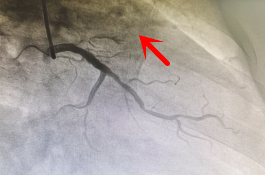

【前降支闭塞开通后造影】

2022年3月初,60岁的聂叔叔,因“阵发性胸闷胸痛1月,加重3天入院”,住院期间行冠脉造影检查示左前降支主支自开口完全闭塞,TIMI血流0级。经过我科介入团队通力合作,历时2小时成功开通患者前降支闭塞病变。术后胸闷痛症状明显缓解,日前已顺利出院,生活质量较前提高。